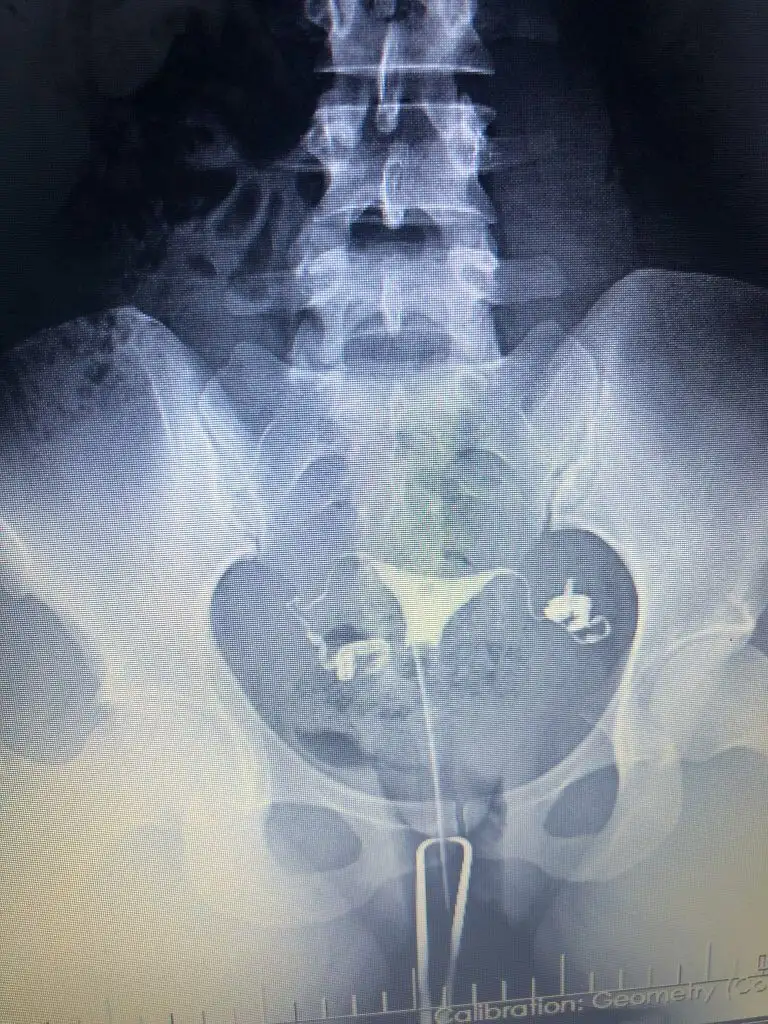

Cok teşekkür ederim.Nasil atabilirim bir bakayim cd de aldim görüntüyü yarin bilgisayardan atmayi deneyeyim bir. Kuşku birakan nedir nededi doktor.ben iki farkli doktora gittim ikiside ayni yorumu yapti. Sıvı dolu olan tüp bosaltilsa bile tekrarlama riski yüksek yani bu demek oluyor ki bosaltilr tüpü denedik bebek yapmayı olmadi herşey basa saracak tekrar hsg cekilecek kapandi mi diye gibi. Bu nedenle sıvı dolu tüpün alınması ortak karardi. Diğer tıkalı olan tüp ise hsg cekilirken doktorum zaten acmaya calismisti açılmamışti ameliyat sırasında da ilk oncelik onu açmaya calismak oldu ama geride bir dermoid kist (ameliyat sırasında görülebildi) tüpü tikamis ve acmays çalıştiklarinda tüpe basinc nedeniyle zarar vermis oyuzden oda alındı.İyi dileklerim sizinle

Özelden hsg görüntünüzü bana atar mısınız sakıncası yoksa ben iki kere çekildim normal raporlandı ama bir doktor aklımda kuşku bıraktıbu yüzden araştırma içine girdim, iki aşılamam negatif oldu

Ben Funda hanıma görselleri attığımda problem olduğunu düşünmüyorum dedi, ben çok fazla doktora gittim Çünkü bir neden bulunamıyordu yalnızca biri hidroselpenks dedi ve laparoskopi önerdi ben de o an çok şaşırıp çıktım. O yüzden bu durumu yaşayanlara mutlaka soruyorumCok teşekkür ederim.Nasil atabilirim bir bakayim cd de aldim görüntüyü yarin bilgisayardan atmayi deneyeyim bir. Kuşku birakan nedir nededi doktor.ben iki farkli doktora gittim ikiside ayni yorumu yapti. Sıvı dolu olan tüp bosaltilsa bile tekrarlama riski yüksek yani bu demek oluyor ki bosaltilr tüpü denedik bebek yapmayı olmadi herşey basa saracak tekrar hsg cekilecek kapandi mi diye gibi. Bu nedenle sıvı dolu tüpün alınması ortak karardi. Diğer tıkalı olan tüp ise hsg cekilirken doktorum zaten acmaya calismisti açılmamışti ameliyat sırasında da ilk oncelik onu açmaya calismak oldu ama geride bir dermoid kist (ameliyat sırasında görülebildi) tüpü tikamis ve acmays çalıştiklarinda tüpe basinc nedeniyle zarar vermis oyuzden oda alındı.

Benimkine hic benzemiyorBen Funda hanıma görselleri attığımda problem olduğunu düşünmüyorum dedi, ben çok fazla doktora gittim Çünkü bir neden bulunamıyordu yalnızca biri hidroselpenks dedi ve laparoskopi önerdi ben de o an çok şaşırıp çıktım. O yüzden bu durumu yaşayanlara mutlaka soruyorum

Ben İzmir’de değilim ama bir ayağım İzmir’de bu yüzden medikal aklımda olan bir yerdi buna istinaden kendisi ile yazıştım.Benimkine hic benzemiyorhidrosalpkinks diyen hangi doktor. Benim hsg cekimini yapan doktor Mehmet Bal ameliyatimida o yapti. Ama Funda hocaya hsg filmlerini göstermiş , Funda hanima o yolendirdi beni zaten. Ben bir de Engin Sarıca' ya gittim hsg raporumu götürdüm inceledi oda ayni yorumda bulundu

Yani acikcasi benimkini hatırladığım kadariyla ve simdi google dan baktığım diger örnek hidrosalpkinksler gibi degil görüntün yani bende boyle şiş bir yer gorunuyordu resmen. Hsg cekilirken ağrın oluyor mu ? Mesel ben tupleri acik olanlarda cok agrisi oluyor diye duymadim. Ben agridan mahvolmuştm ki anestezili cekilmeme rağmen. Bence normal gibi görünüyor tüplerin ama güvendiğin bir doktor varsa ve sartlaro cekimi iyi olan bir yer agrinda olmuyorsa için rahat etsin diye tekrar cektirebilirsin. Ama bence hic gerek yok bir kaç doktor ayni yorumu yaptiysa eğerBen İzmir’de değilim ama bir ayağım İzmir’de bu yüzden medikal aklımda olan bir yerdi buna istinaden kendisi ile yazıştım.